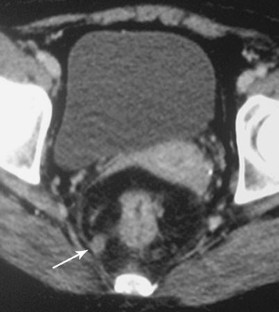

Fig. 1

Fig. 2

Fig. 3

Fig. 4